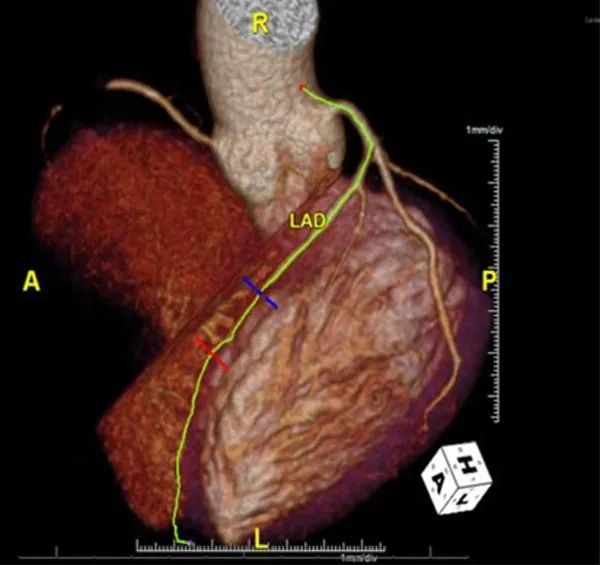

冠脉CTA显示非钙化性斑块,右冠状动脉中段完全闭塞,左前降支近段狭窄不到30%,左前降支中段狭窄低于50%(图1)。尽管冠脉CTA显示有冠心病,但其总冠脉钙化评分为0。

图1. 冠脉CTA影像。